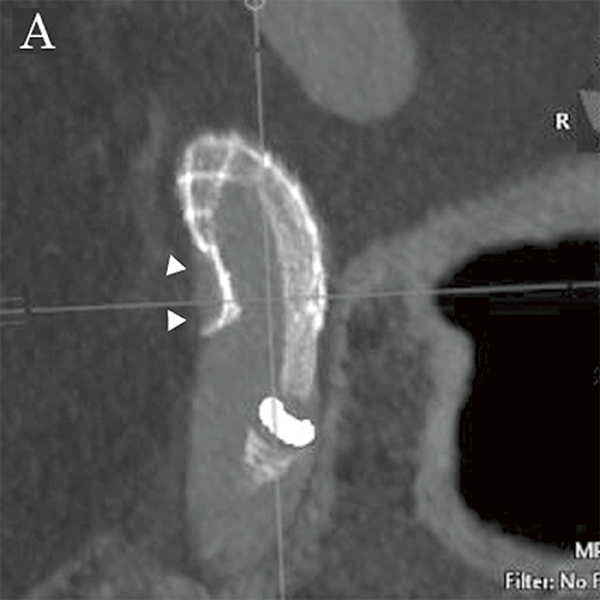

На основі цих вимірювань було обрано пристрій для емболізації Pipeline™ (PED) (4,75 мм × 16 мм; Medtronic, Японія), аневризму лікували, спостерігаючи за флюорографічними зображеннями детектора високої чіткості (мал. 5A та 5B). Пристрій було розгорнуто від C2 (біфуркація задньої сполучної артерії) до C4, а розгортання FD і стан кримпування материнської судини підтверджено Alpha CT (мал. 6A і 6B).

Малюнок 6A: Проекція максимальної інтенсивності Alpha CT після розміщення FD.

Малюнок 7A: Мультипланарна реконструкція Alpha CT після розміщення FD. Стрілками показано ознаки поганого розгортання (довга вісь на проксимальному кінці).